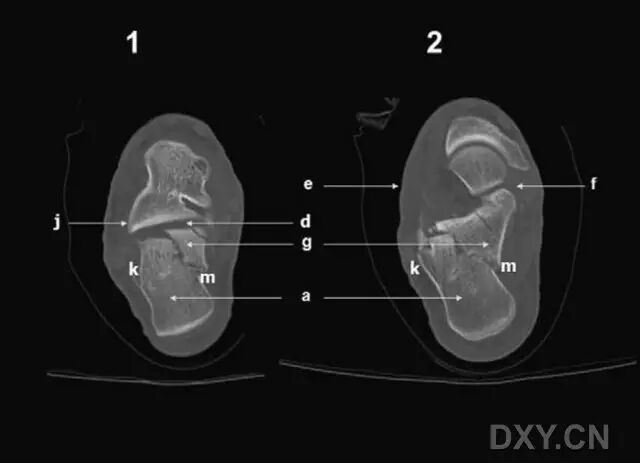

跟骨解剖非常复杂,在三维上,存在多条关节轴线(图 1)。跟骨后关节面呈凸起状,并向后内侧倾斜以支撑距骨体。前、中关节面则呈扁平状,分别支撑距骨头和颈部。载距突位于前中关节面的内侧,为一坚硬的骨性凸起,在进行内固定时,是理想的螺钉拧入位点(图 2 和 3)。

图1 跟骨后面观(如图所示,在三维空间中,包括跟骨结节、距下关节和跟骨内外侧皮质的轴线走行方向各异。a: 跟骨结节;d: 距下关节后部;f: 跟骨-距骨颈关节的内侧面;g: 载距突;k: 外侧皮质;m: 内侧皮质。)

图2 跟骨内侧面观。a: 跟骨结节;b: 前凸;d: 距下关节后部;f: 跟骨-距骨颈关节的中间关节面;g: 载距突;h: 拇长屈肌腱沟;m: 内侧皮质。